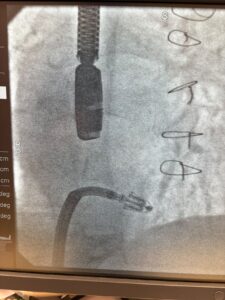

A PASCAL Tricuspid case was successfully performed at LAU Medical Center, Beirut marking another step forward in structural heart interventions. We are proud to have supported this achievement with the PASCAL transcatheter valve repair system, reinforcing our commitment at IntelMed to delivering minimally invasive solutions that enhance patient care.

Thank you to Dr. Georges Ghanem and the dedicated medical team for driving innovation in structural heart therapy.